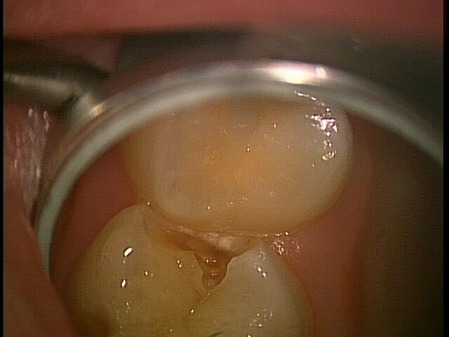

この写真は乳歯が虫歯になっているんだけど。。。隣のノーマルな歯が押してきているように感じるのは私だけでしょうか?